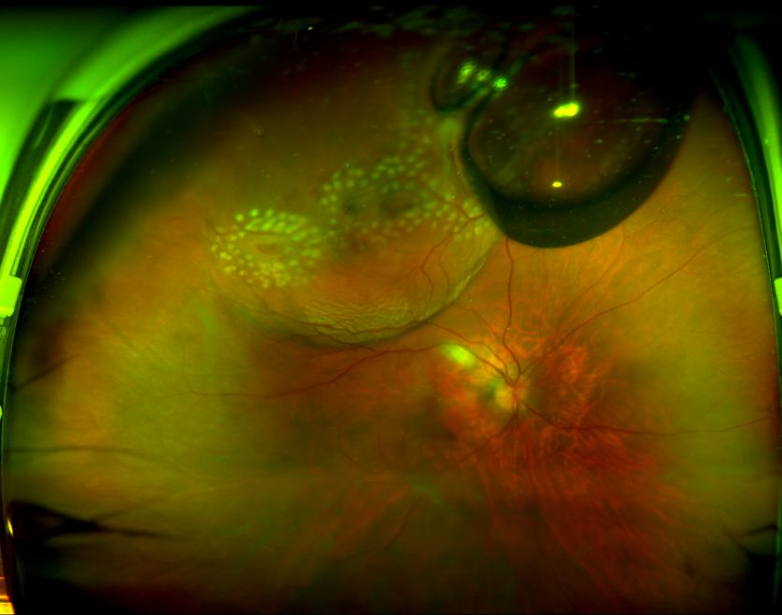

经过详细的专科检查,结果显示:她的右眼视网膜脱离已波及黄斑区,周边视网膜还有两处巨大裂孔,一处约2个视盘直径大小,一处约6个视盘直径大小,视网膜已呈现青灰色隆起,左眼也呈现出网格样变性区。深圳爱尔眼科医院院长王建文教授诊断为:右眼孔源性视网膜脱离。

经过采取三维重建计算方式和精准判断裂孔位置,提高复位裂孔的正确性和复位率。8月24日,王建文教授为张姐右眼实施了“折叠球囊(FCB)巩膜顶压术”,术中注水2.0ml、玻璃体注气0.6ml,成功将脱离的视网膜“顶”回原位。整个手术过程顺利,仅用时20分钟。目前,张姐的视力已恢复至1.0。

术前

术后第二天激光后